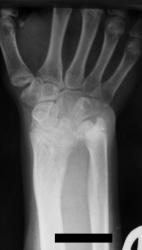

Девочка 14 лет. Ранее за помощью не обращались. Только в этом возрасте родителей и саму пациентку начала беспокоить деформация предплечий.

Рентгенологическая классика для болезни Маделунга:

1. Укорочение лучевой кости.

2. «Скошенность» суставной поверхности дистального эпифиза лучевой кости в ладонную и локтевую сторону, что «симулирует» визуально подвывих костей запястья.

3. «Нависание» полулунной кости над ладонным краем дистального эпифиза лучевой кости.

4. Высота дистального эпифиза по лучевой стороне превосходит его высоту по локтевой стороне.

5. В результате раннего закрытия ростковой зоны по локтевой и ладонной стороне, формируется ладонный и локтевой наклон суставной поверхности.

6. Деформация и изменение расположения проксимального ряда костей запястья, по форме, напоминающей «клин», вершиной которого является полулунная кость.

7. Головка локтевой кости находится в положении «вывиха» и смещена в «тыльном» направлении, по отношению к лучезапястному суставу.